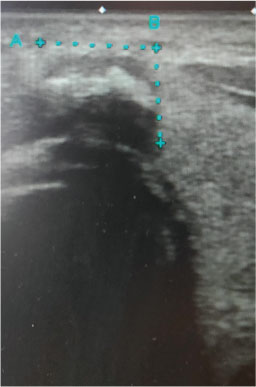

# 乳頭癌疑い

<頸部超音波検査>

・乳頭癌疑い(Class III)